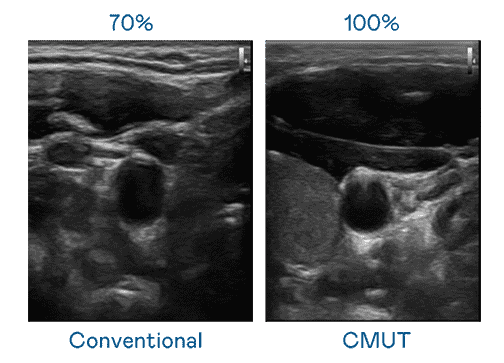

CMUT 技术是一种用电容式微机电元件来产生超音波讯号的技术。。。与传统 PZT 压电式技术相比,,,,CMUT 频宽增加 30%,,,更宽频的超音波讯号让影像解析度大幅提升,,是实现高影像品质医疗超音波扫描、、促进精准医疗发展的关键技术。。。

大频宽带来超清晰影像

超音波影像的解析度高低,,首先取决于探头能发出的讯号频宽。。。。z6尊龙 CMUT 可提供高清晰的超音波讯号,,,,提供高频宽、、、、高灵敏度、、影像纹理细节更高的超音波影像,,协助医护人员缩短影像判读时间及利用精准的医疗影像进行诊断。。。